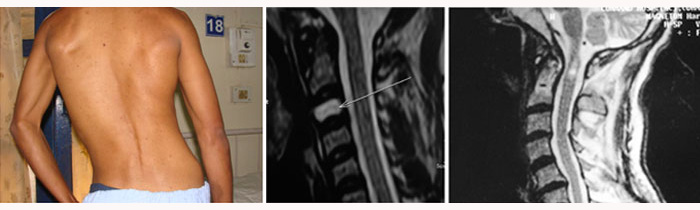

Posttraumatic syringomyelia

Posttraumatic syringomyelia is an uncommon cause of late neurological deterioration in a patient with spinal cord injury. The pathology has received recent attention due to increased physician awareness and the availability of MR imaging. The underlying mechanism is probably local arachnoid scarring and obstruction to CSF flow, followed by seepage of CSF through the Virchow-Robin spaces. Persistent deformity predisposes to formation of posttraumatic syrinx. Anatomical decompression, division of arachnoid scarring, correction of spinal deformity and shunting procedures are measures to arrest the progress of the syrinx.

Click here to read full article